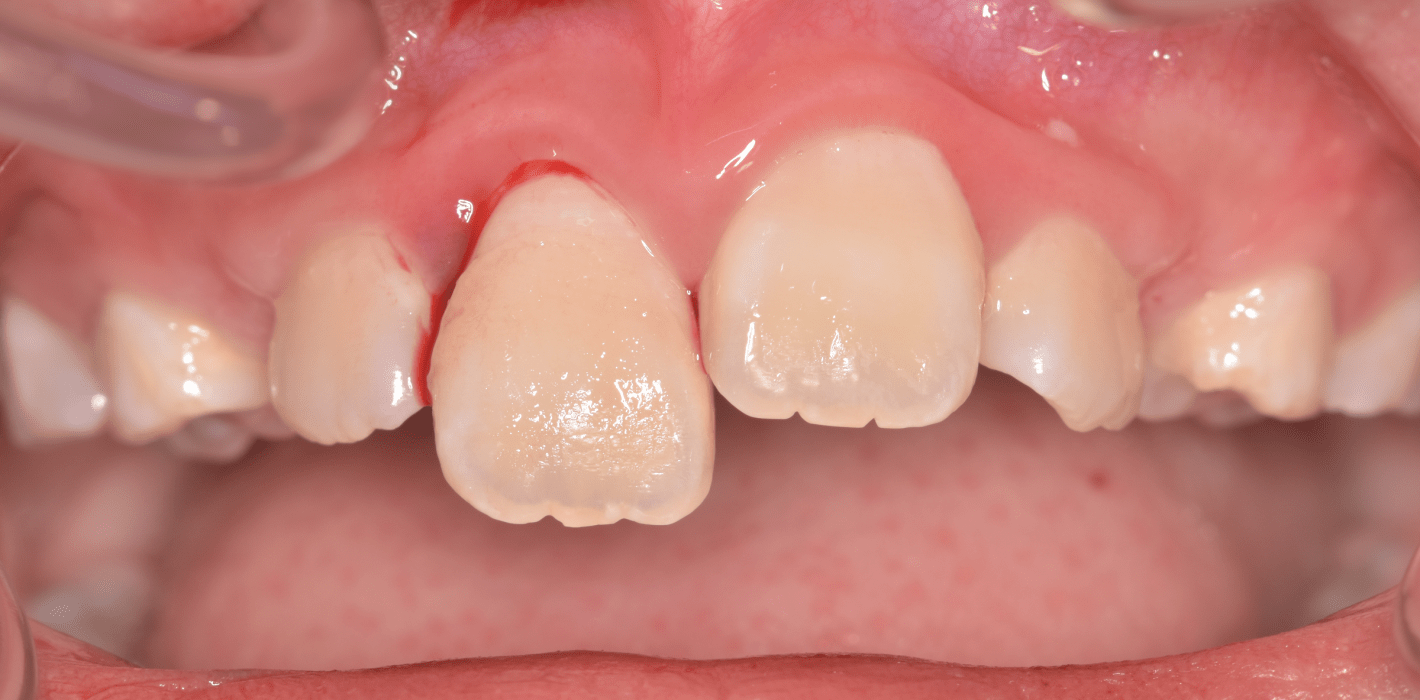

Zu den Zahnfrakturen mit Pulpabeteiligung gehören die in das Dentin reichende unkomplizierte Kronenfraktur sowie die komplizierte Kronenfraktur mit Pulpaexposition. Rein schmelzbegrenzte Frakturen sind hinsichtlich des Pulpastatus als unkritisch einzuschätzen.1 Dislokationsverletzungen betreffen die Pulpa insofern, als das Gefäß-Nerv-Bündel je nach Ausprägung der Positionsveränderung gestaucht, gedehnt oder abgerissen sein kann. Bei Zähnen mit abgeschlossenem Wurzelwachstum geht man davon aus, dass spätestens ab einer Dislokation von 2 mm die Pulpa abgerissen wurde, was die zeitnahe Einleitung der Wurzelkanalbehandlung notwendig macht.2, 3 Bei geringer ausgeprägter Dislokation kommt den Nachkontrollen eine wesentliche Rolle zu, bei denen jeweils dem Pulpastatus besonderes Augenmerk zukommen sollte, um eine Pulpanekrose frühzeitig zu detektieren.

Zu den wesentlichen diagnostischen Verfahren, die zur Erfassung des Pulpastatus herangezogen werden, gehören neben der Inspektion und der röntgenologischen Bildgebung die Sensibilitätsprüfung sowie der Perkussionstest. Der Inspektion kommt insbesondere bei der Erstbehandlung eine wesentliche Rolle zu. Hierbei wird abgeklärt, ob es sich bei Zahnfrakturen um eine schmelzbegrenzte Verletzung handelt, ob das Dentin mitbetroffen und ob zusätzlich die Pulpa exponiert ist. Bei Dislokationsverletzungen wird das Ausmaß der Positionsveränderung erfasst und ob zusätzliche Gewebe wie Knochenstrukturen oder umliegende Weichgewebe betroffen sind. Auch können Farbveränderungen des Zahnes erfasst werden. Die Röntgendiagnostik zum Zeitpunkt des Unfalles gibt Aufschluss über die Größe des Pulpenkavums und das Lumen des Wurzelkanals, den Stand des Wurzelwachstums und die periapikalen Verhältnisse. Des Weiteren finden sich möglicherweise Hinweise auf eine Wurzelfraktur.

Bei Pulpaexposition ist die oberste Prämisse der Erhalt der Vitalität des Zahnes. Vor allem bei jungen Patienten und bei nicht abgeschlossenem Wurzelwachstum, aber auch bei erwachsenen Patienten ist die Vitalerhaltung die Methode der Wahl. Dabei spielen die Dauer und die Größe der Exposition keine wesentliche Rolle.10 Die oberste Gewebeschicht sollte zunächst im Sinne einer Mikropulpotomie angefrischt werden, was mit einem Diamantschleifer unter Wasserkühlung durchgeführt werden kann. Nach Blutstillung, zu der Natriumhypochlorit tropfenweise appliziert werden kann, wird das Sistieren der Blutung kontrolliert. Ist dies verifiziert, wird ein biokompatibles Material in direktem Kontakt mit dem Gewebe aufgebracht und der Zahn anschließend adhäsiv verschlossen.10 Dauert die Blutung an, beispielsweise weil der Unfall bereits mehr als 24 Stunden zurückliegt, kann tiefer pulpotomiert werden. Da eine traumatisch geschädigte Pulpa in der Regel vor dem Unfall gesund war, ist die Heilungskapazität meist sehr gut.11 Auch bei bestehender Exposition zur Mundhöhle hin über einen Zeitraum von Tagen kann die Pulpotomie noch hohe Erfolgsraten erzielen.

Tierexperimentelle Studien konnten zeigen, dass selbst bei über mehrere Tage hinweg freiliegender Pulpa Bakterien aus der Mundhöhle nicht tiefer als 2 mm in das Gewebe eindringen konnten.12 Kritisch ist dabei die erfolgreiche Blutstillung, die nach ca. fünf Minuten erreicht sein sollte. Die Erfolgsquoten der Pulpotomie nach Zahntrauma liegen deutlich über denen der direkten Überkappung bei über 90 Prozent. Dies ist auch in der revidierten Fassung der S2k-Leitlinie zum dentalen Trauma bleibender Zähne herausgestellt.3 Es ist zu beachten, dass bei begleitender Dislokationsverletzung die Durchblutung der Pulpa eingeschränkt oder sogar komplett unterbunden sein kann, was das Risiko des Misserfolges vitalerhaltender Maßnahmen signifikant erhöht.13 Daher sollte in solchen Fällen die Pulpektomie durchgeführt werden. Dies gilt ebenso bei umfangreichem Hartsubstanzverlust, wenn die definitive Restauration zusätzlich intrakanalär verankert werden muss.